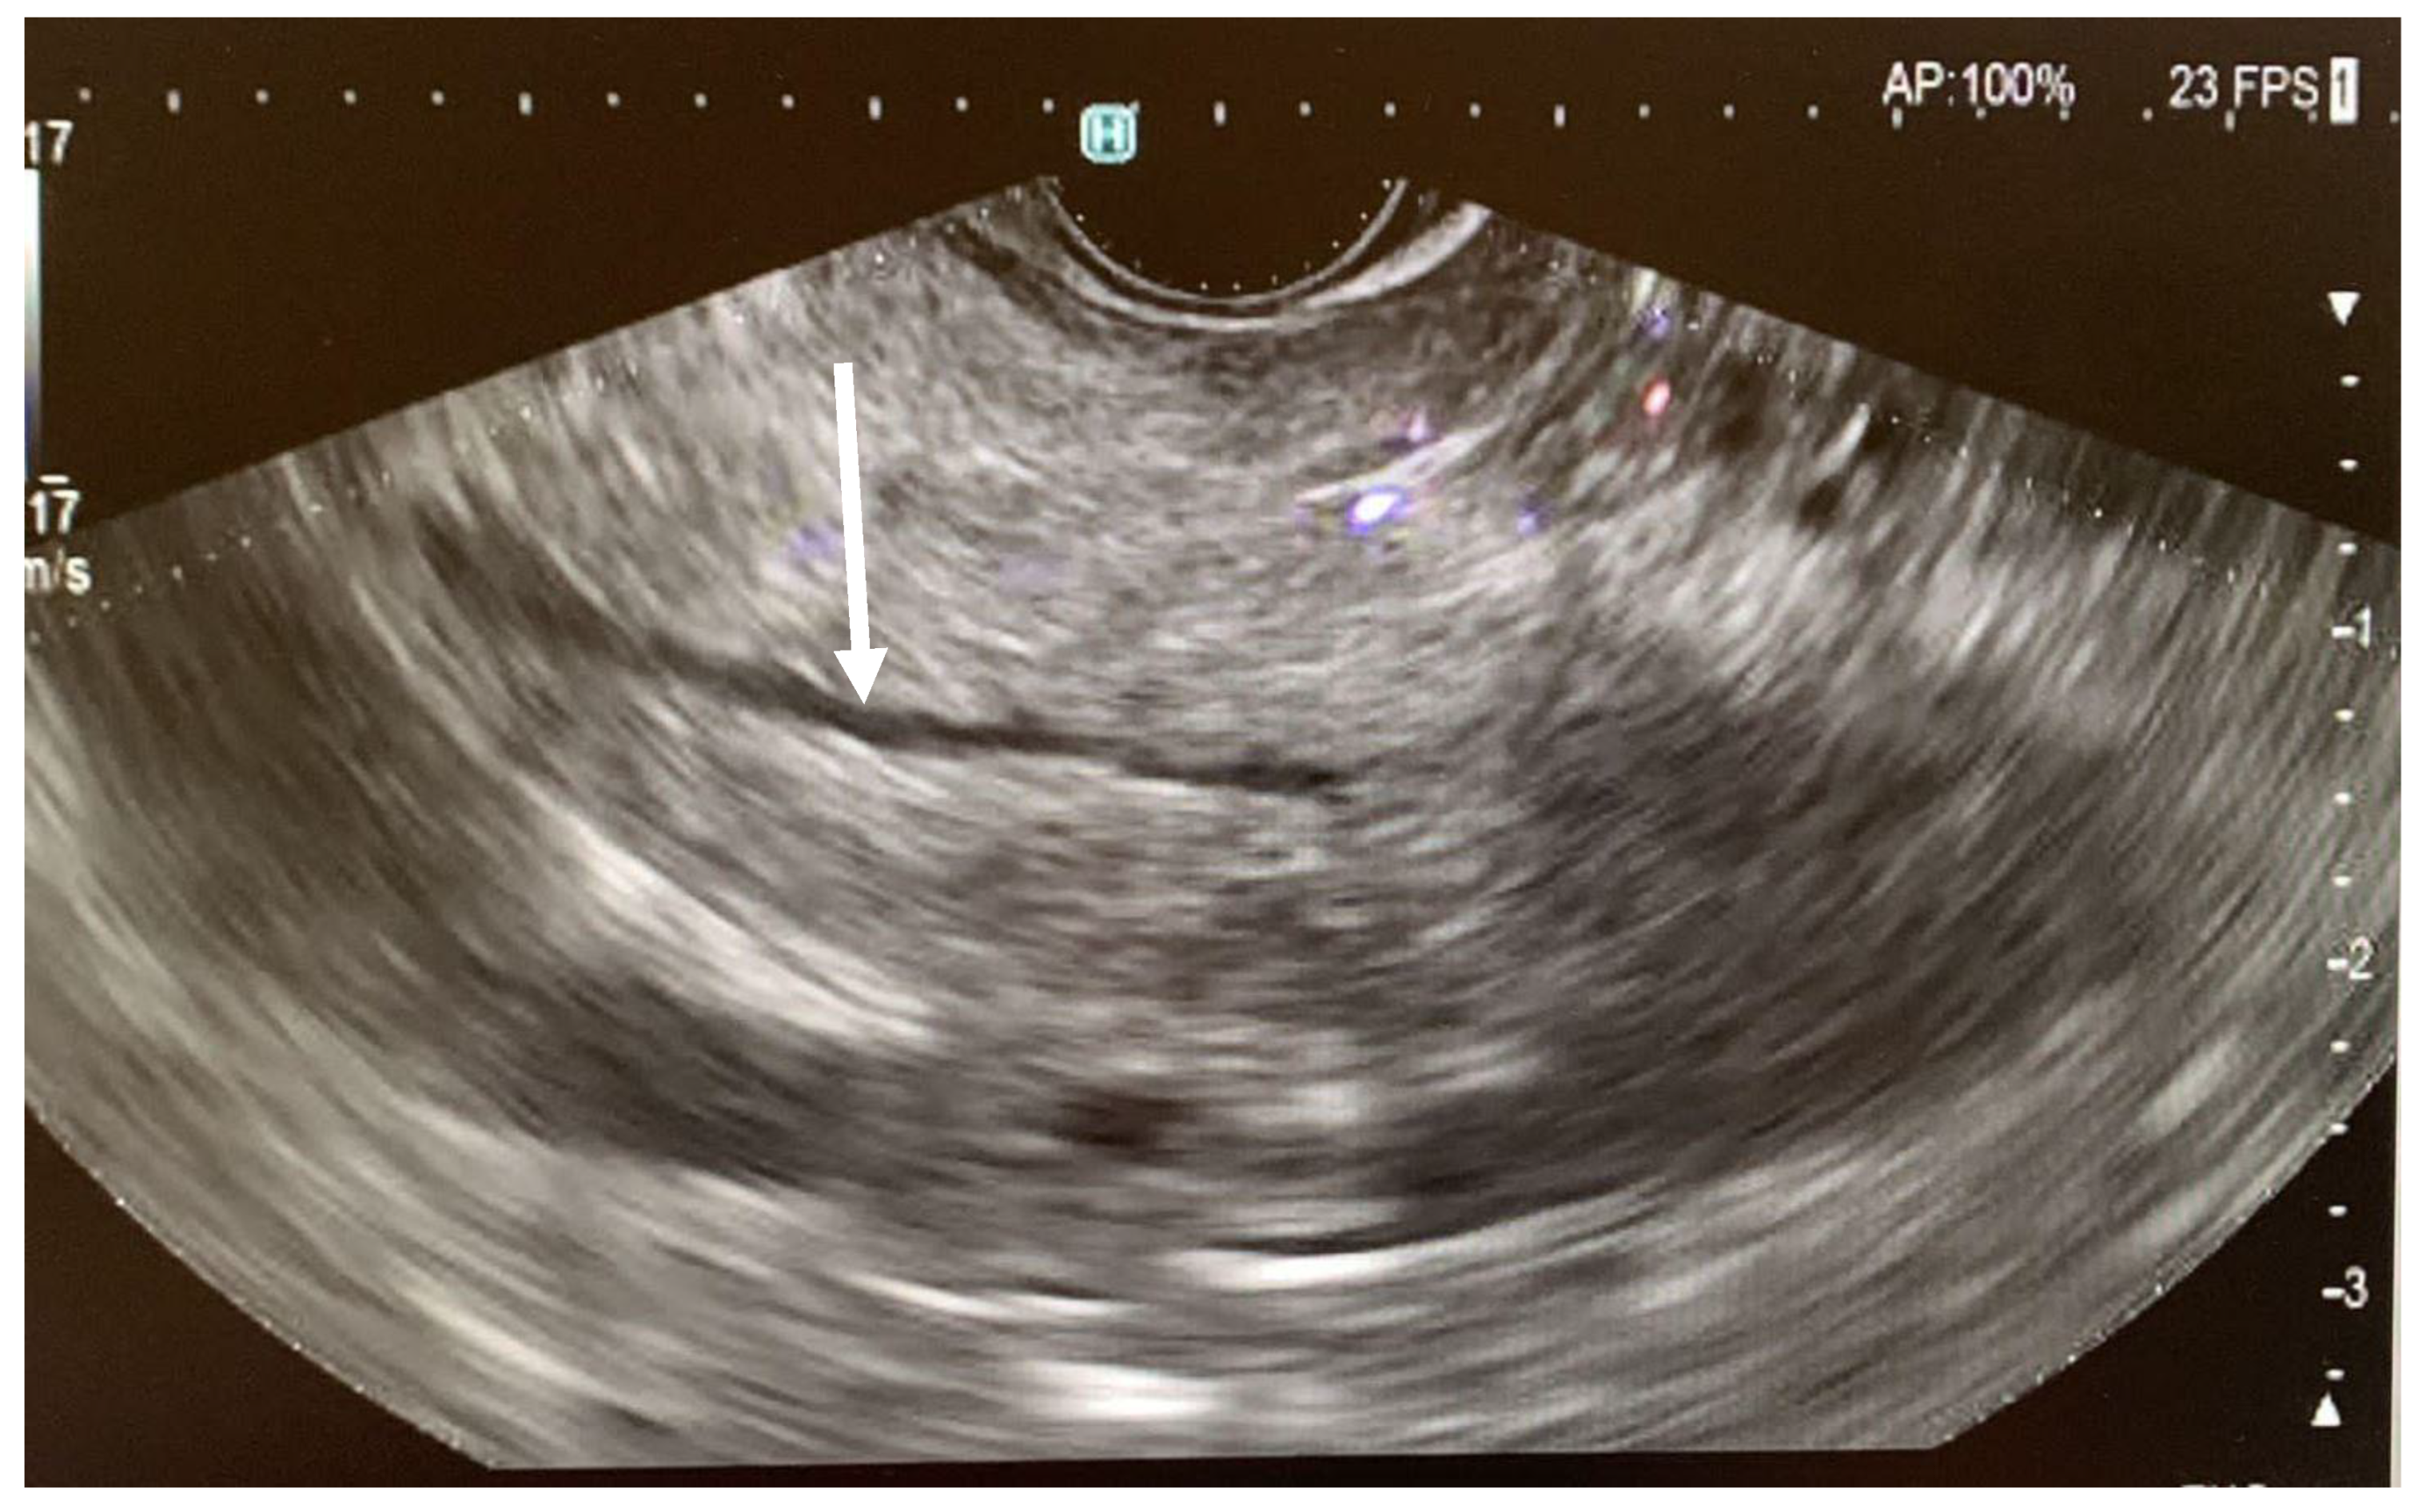

- Three endosonographic criteria have been suggested for the diagnosis of pancreas divisum with endoscopic ultrasound: (a) Inability to follow the main pancreatic duct from the major ampulla to the pancreas body; (b) Inability to follow the main PD from the hypoechoic ventral pancreas to the hyperechoic dorsal pancreas [40]; (c) The presence of the Stack sign as a possibility of pancreas divisum. The Stack sign is visualized better by positioning the radial echoendoscope (or by linear echoendoscope, reverse Stack sign) in the long scope position with the transducer in the duodenal bulb. When the balloon is inflated and advanced snugly into the apex of the bulb, the bile duct (closest to the transducer) and the pancreatic duct can be seen running in parallel through the pancreatic head [26,41]. Performing EUS, the Stack sign refers to the parallel alignment of three tubular structures seen in the region of the pancreatic head: common bile duct (CBD), ventral pancreatic duct (Wirsung’s duct), and dorsal pancreatic duct (Santorini’s duct). In pancreas divisum (positive Stack sign): the ventral and dorsal pancreatic ducts remain separate and on EUS, three parallel, stacked tubular structures are evident: (a) the CBD (most anterior); (b) the ventral pancreatic duct (Wirsung); (c) the dorsal pancreatic duct (Santorini) (most posterior). This triple-duct alignment is indicative of non-fusion and suggests pancreas divisum.